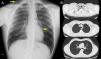

Se realizó analítica sanguínea completa con hemograma y proteinograma sin alteraciones; en la bioquímica se objetivaron niveles de vitamina B12 en 172,1pg/ml. La radiografía de tórax a su llegada (fig. 1A) evidenció un área de hiperclaridad paracardíaca izquierda compatible con neumomediastino a dicho nivel. Se decidió realización de TAC torácica para confirmar diagnóstico y completar estudio.

A) Radiografía de tórax del paciente, en la que se aprecian (señalados con flechas) signos de enfisema subcutáneo a nivel laterocervical derecho y área de hiperclaridad paracardíaca izquierda, sugestiva de neumomediastino. B) TAC torácica (ventana parénquima) en la que se aprecia, a varios niveles, el extenso neumomediastino que disecaba las estructuras mediastínicas.

La TAC (fig. 1B) señalaba como hallazgos más significativos la presencia de un extenso neumomediastino que disecaba las estructuras mediastínicas y se extendía por la cisura mayor izquierda. Además, se acompañaba de enfisema subcutáneo en ambas regiones laterocervicales, huecos supraclaviculares (con predominio izquierdo) y ambas regiones axilares. No se observaron neumotórax ni fracturas costales.